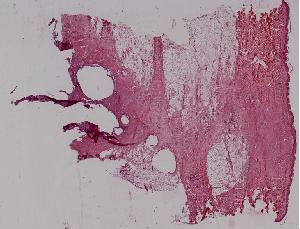

低倍视野